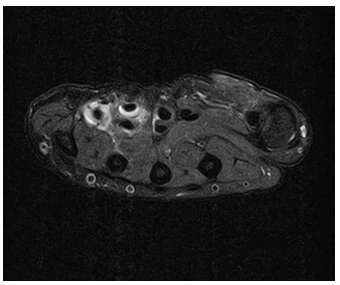

Herein is reported the case of a 15-year-old female adolescent followed at the Orthopedic Outpatient Clinic due to chronic hand pain following trauma to the right hypothenar region and flexor carpi ulnaris one year before. She was admitted to the Pediatric Emergency Department (PED) at the time of trauma and conservatively managed. In the following months, the girl returned to PED with similar pain complaints. X-ray imaging revealed no signs of additional hand injury, but the girl was referred to the outpatient clinic for further study. Magnetic resonance imaging (MRI) showed tenosynovitis of the common flexors of the right hand and rupture of the superficial flexor tendon of the small finger (Figures 1 and 2). The patient initially underwent physical therapy with no significant relief. She was ultimately proposed for surgery and underwent pulley release and synovectomy of the flexor tendons in a private clinical facility, being lost to follow-up. Five months after surgery, she returned to PED with persistent right hand pain. She shared the histopathological report previously performed, which evidenced severe chronic synovitis of the flexor tendons of the right wrist and caseous central-necrotic granulomas, highly suggestive of tuberculous disease. Acid-Fast stain was negative. Personal history was again carefully retrieved, but no known contacts with active or past disease or recent traveling outside the country were identified. The etiological study was continued, with no relevant findings in chest radiography but positive results in both Tuberculin Skin Test and Interferon-Gamma Releasing Assay. At this point, tuberculous involvement of the flexor tendons of the right hand with concurrent chronic synovitis was assumed. The patient complied with 12-month anti-tuberculous chemotherapy with isoniazid, rifampicin, pyrazinamide, and ethambutol for two months, followed by isoniazid and rifampicin for ten months. Five years after the initial hand trauma, the patient remained under clinical surveillance, with persistent chronic pain and intermittent paraesthesia of the right hand, although less severe than before treatment. Additionally, functional limitation of flexion of the 4th and 5th fingers of the right hand persisted as a chronic synovitis complication (Figure 3).

Figure 1 Magnetic resonance imaging of the wrist. Axial T2 fat saturation image showing hyperintense signal surrounding the flexor tendons of the 4th and 5th fingers, with partial rupture of the 5th finger tendon, suggesting traumatic tenosynovitis.